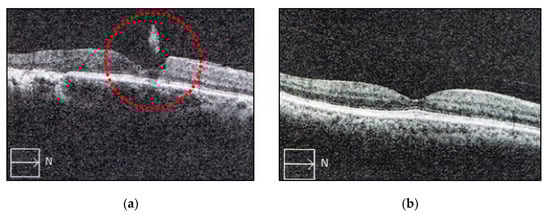

3.2. The Effect of Fruit Enzymes on the Change of Various Floaters